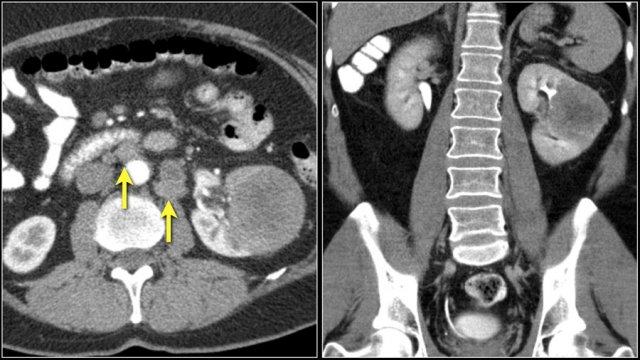

Đây là hình ảnh của một bệnh nhân ung thư phổi.

Có một tổn thương di căn ở thận trái và nhiều tổn thương di căn hạch bạch huyết (mũi tên).

Nếu đây là biểu hiện duy nhất, sẽ rất khó để phân biệt với ung thư biểu mô tế bào thận có di căn hạch bạch huyết.